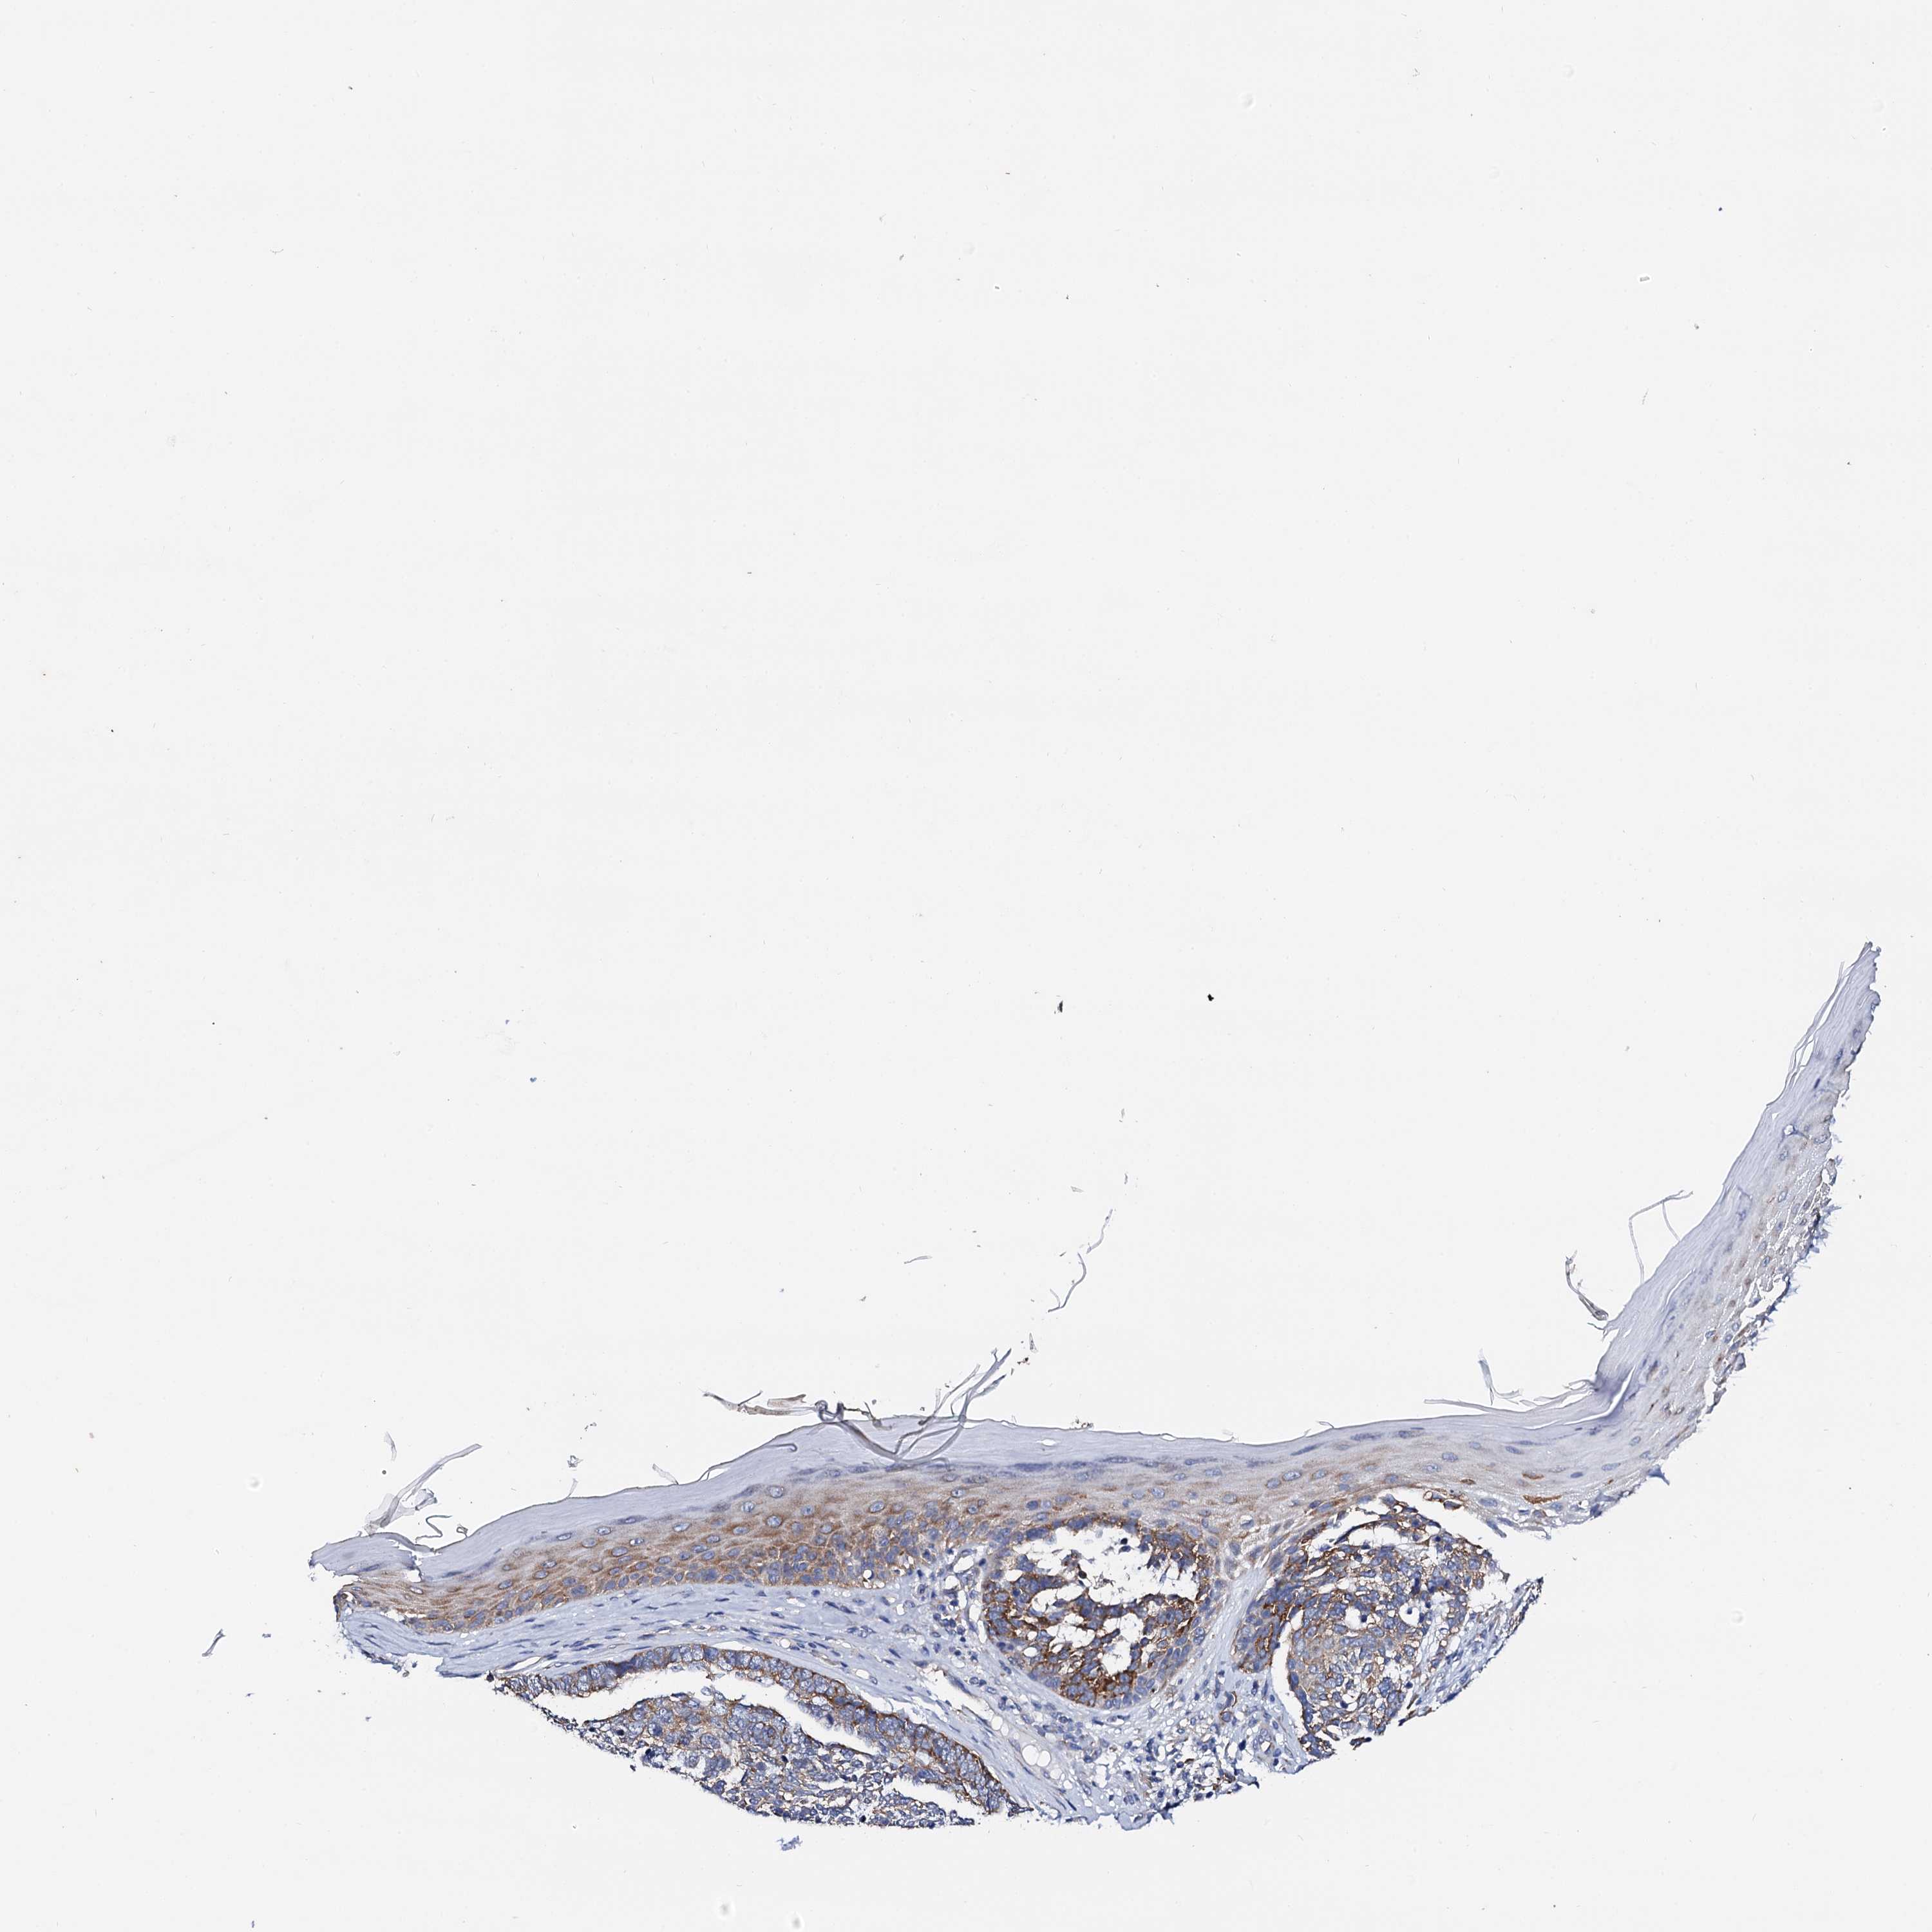

SKIN CANCER - Protein expressioni

A mouse-over function shows sample information and annotation data. Click on an image to view it in a full screen mode. Samples can be filtered based on level of antibody staining by selecting one or several of the following categories: high, medium, low and not detected. The assay and annotation is described here.

Antibody staining in the annotated cell types in the current human tissue is reported as not detected, low, medium, or high, based on conventional immunohistochemistry profiling in selected tissues. This score is based on the combination of the staining intensity and fraction of stained cells.

Each image is clickable and will lead to virtual microscopy that enables deeper exploration of all samples and also displays staining intensity scores, fraction scores and subcellular localization as well as patient and tissue information for each sample.

Antibody HPA039360

Intensity

Strong

Moderate

Weak

Negative

Quantity

>75%

75%-25%

<25%

None

Location

Nuclear

Cytoplasmic/membranous

Cytoplasmic/membranous,nuclear

Basal cell carcinoma

Squamous cell carcinoma, NOS

Squamous cell carcinoma, metastatic, NOS